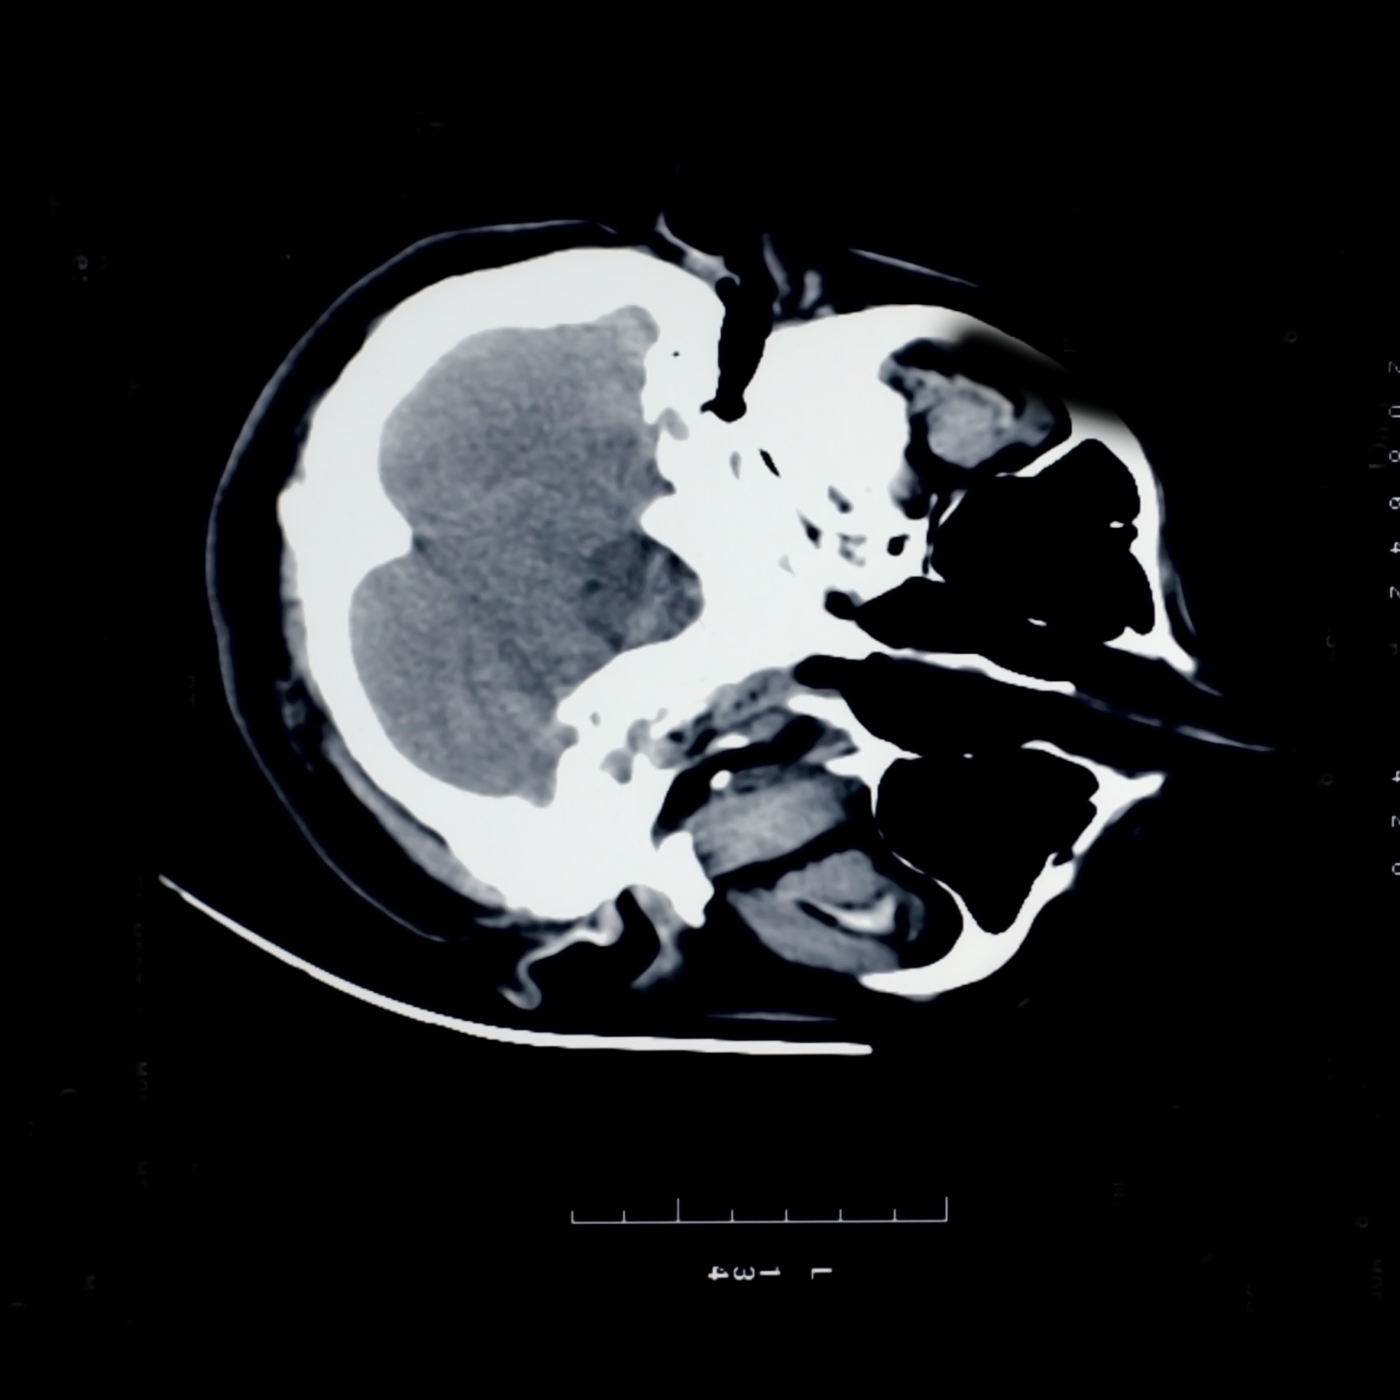

CT Scan

Computerized Tomography or CT Scan is also another commonly recommended test by doctors to check on the exact location of blood clots, bone tumors and fractures and it is also essential for keeping a check over diseases such as Cancer. Hence it is also a very important service that would be essential for the people. So we are always there for your medical and diagnostic needs and proudly present to you our 24/7 CT Scan services.